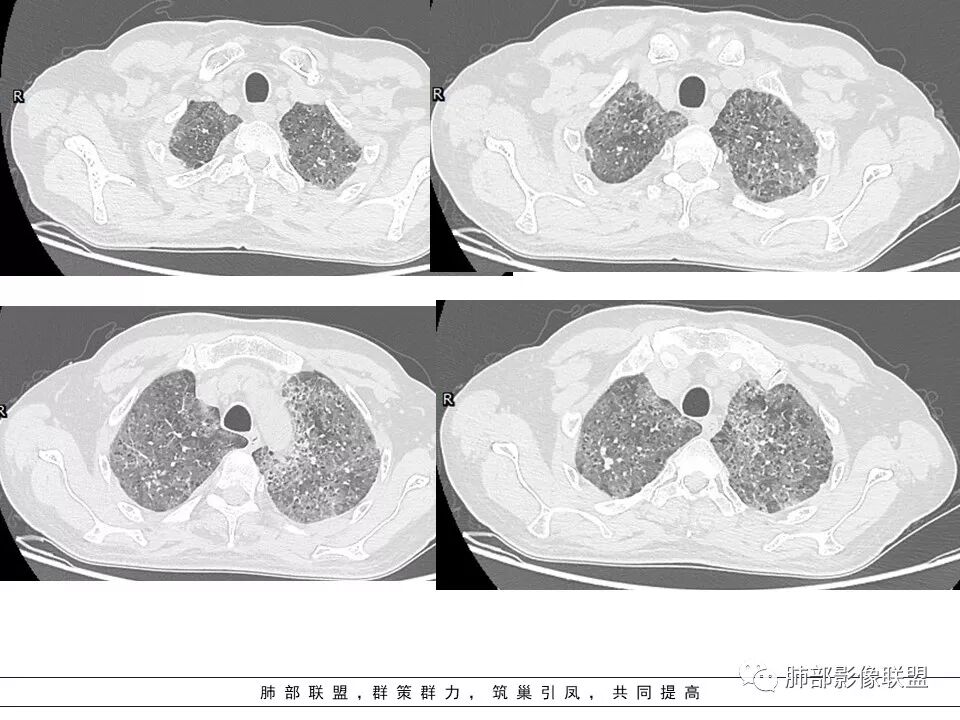

上肺为主小叶中心型肺气肿——吸烟

碎石路征,下肺为主

肺血坠积

南边:只有GGO+网格(小叶间隔增厚),然后就是分布的问题

1、GGO+网格——碎石路征

2、分布无特定位置,较随机

3、可有少许实变——部分与层厚有关

4、小叶间隔内静脉增粗

5、病灶较多时部分可见重力趋势

6、很少有纤维化改变

1.由于脂蛋白的沉积和占据,肺泡腔含气量减少,这是影像上较大范围“磨玻璃影”的基础。

2.由液体、细胞浸润和纤维组织造成的小叶间隔增厚是影像上多边形“铺路石征”的基础。

3.显眼的小叶间隔对病灶有阻挡作用是形成影像上“地图样改变”的基础。我们观察到的病灶与临近相对正常肺组织之间常常有比较清楚的分界。

这种表现颇具特征性。但有部分患者(1/4)仅有磨玻璃影而未显示小叶间隔增厚,这种情形我们很难将PAP列为第一诊断。

4.病灶常多发,但心尖区及膈角区相对轻微。

5.部分病例显示有局部实变影

6.不会出现胸水和淋巴结肿大